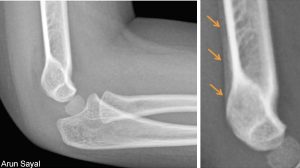

A 3-year-old girl fell while running. An X-ray the day of the fall (LEFT) showed no fracture, but her arm was splinted for possible occult fracture. A follow-up X-ray at three weeks (RIGHT) confirmed the fracture (arrows).